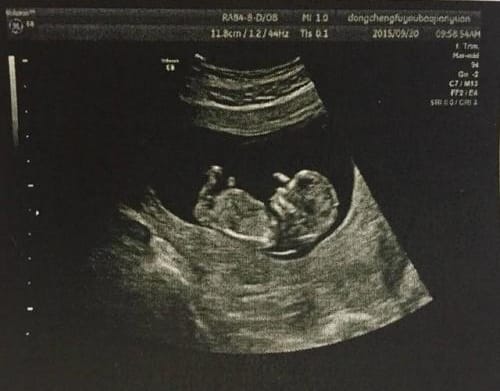

以灰阶即亮度(brightness)模式形式来诊断疾病称“二维显示”,因亮度第一个英文字母是B,故称B超,又称二维超声或灰阶超声。

B型超声检查的范围很广,不同的检查部位,检查前的准备亦不相同。①腹部检查:包括肝、胆、胰、脾及腹腔等。一般应该空腹检查,因为进食后,胃及肠道产生气体,影响超声的穿透,空腹检查效果最好。②妇科检查:应该饮水憋尿,当膀胱充盈后,挤开肠管,让超声更好的穿透到盆腔,清晰的显示子宫及卵巢的正常与异常。③泌尿系检查:应该多饮水,当膀胱充盈后,内部的结石、肿瘤、息肉等,即能更好的显示。④体表肿物及病变:可以即时检查,一般无需特殊准备。⑤心脏及四肢血管检查,亦无需准备。

B型超声是医学影像学超声的主要检查方法,虽然超声的发展突飞猛进,如内镜超声、超声造影、三维成像、弹性成像等等,都是在B型超声基础上发展起来的。因此,凡是进行超声工作的医师及被检查的患者,都应该了解B型超声的临床医学特点、检查前准备、检查范围及注意事项等等,以便更好地应用它来为被检查者服务服务。